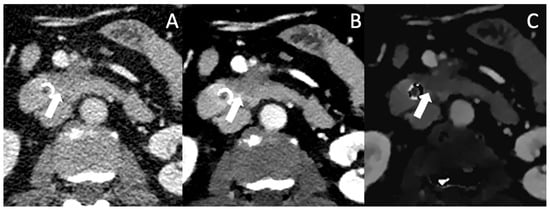

A patient presenting with abdominal pain who received a single-phase protocol is shown in Figure 1, in which VMI and ID show a more clearly visible and well-demarcated lesion of the pancreatic corpus, which was later confirmed to be PDAC. Currently there are no studies directly comparing the benefits of SDCT to MRI in the detection of small or hypoattenuating lesions. However, several studies indicate good diagnostic performance of MRI in lesions <2 cm, with sensitivities ranging from 90 to 100% [45,46]. In particular, DWI has a good diagnostic performance with a sensitivity of 92–96% and specificity of 97–99% [47,48]; however, DWI has its limitations in differentiating mass-forming pancreatitis from PDAC, its similar ADC values [48]. With spectral CT, VMI and IDM can be used to improve the sensitivity and the specificity for the differentiation of mass-forming pancreatitis from PDAC [49].

Figure 1. (A) The conventional CT image shows an ill-defined, moderately hypoattenuating mass of the pancreatic corpus in the portal venous phase (marked with the arrow). In VMI (B) and iodine density maps (C), the hypoattenuating tumor is more clearly visible with sharp demarcation to the adjacent pancreatic parenchyma.